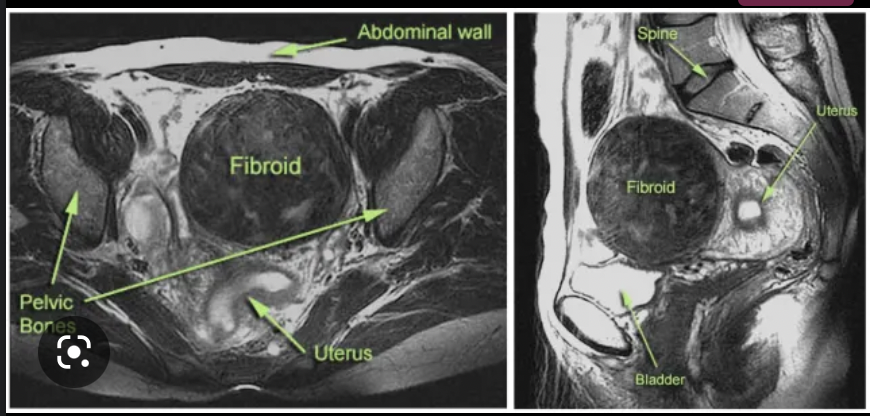

MRI

• can be performed prior to surgery

• provides more information about the size, shape + blood supply of the fibroids